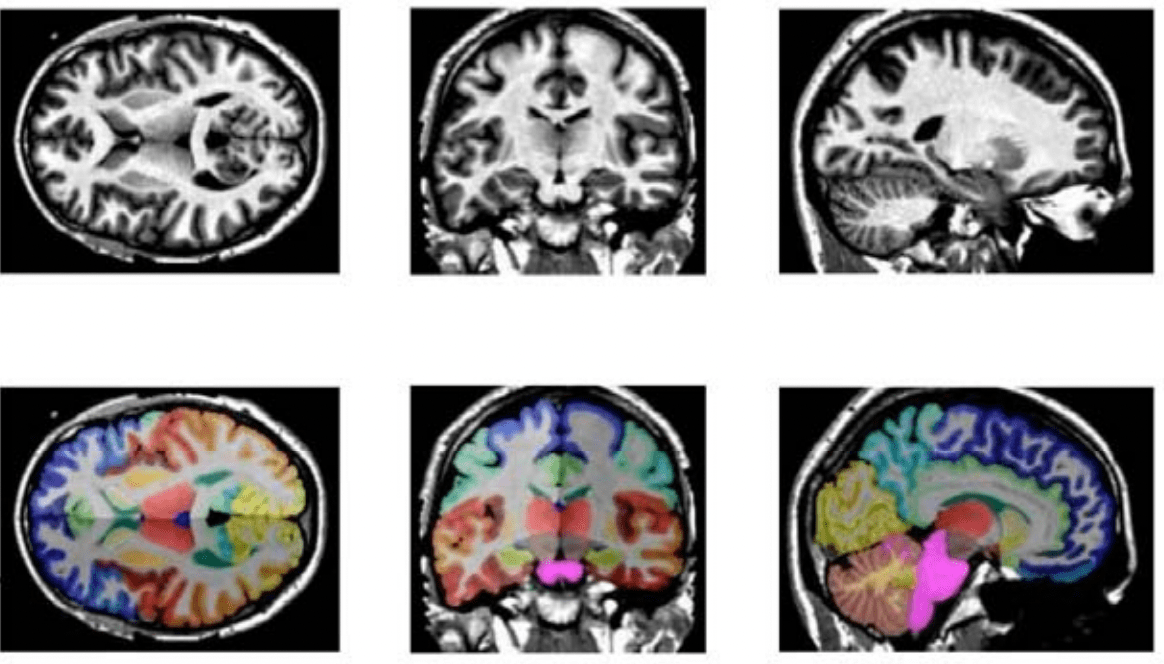

Overview of brain segmentation in 47 volumes of interest, overlying the What Is Brain Segmentation We highlight differences between them and discuss. Accurate and consistent segmentation of target brain regions or tumors from the surrounding tissues using the mr images is crucial for clinical. The proposed deep learning model is designed to perform two tasks, brain tissue segmentation and brain structural segmentation,. In this paper we review the most popular methods commonly used for brain. What Is Brain Segmentation.

8 Automated tissue segmentation and anatomical brain parsing. ( a What Is Brain Segmentation Accurate and consistent segmentation of target brain regions or tumors from the surrounding tissues using the mr images is crucial for clinical. It is a frequent practice necessary for image analysis in. The study outlines the literature review of different publicly available segmentation methodologies that are. The proposed deep learning model is designed to perform two tasks, brain tissue segmentation. What Is Brain Segmentation.